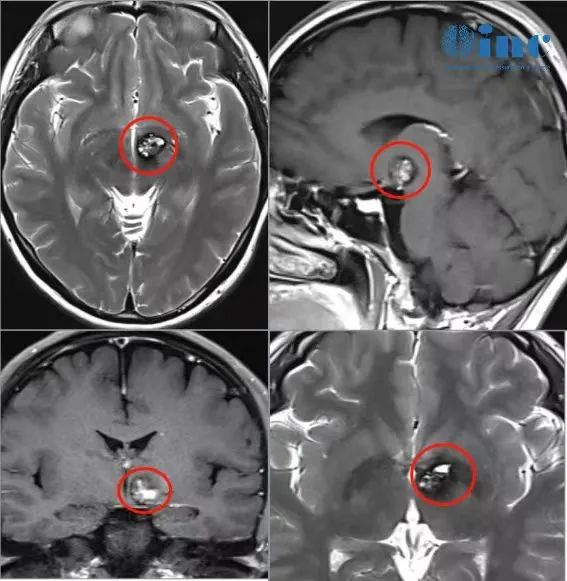

术前术后影像对比

3、肿瘤位置深在,术中导航容易因脑脊液释放引发漂移,术中需以前联合为解剖标记,肿瘤位于前联合后方

经纵裂入路(InterhemisphericCraniotomy)处理下丘脑、中脑病变。纵裂入路开颅术是利用大脑纵裂的自然间隙,进入到大脑镰旁中线深部和脑室旁部位。通过这个自然间隙操作有诸多优点,比如较大限度的降低了对脑组织的牵拉和侵犯。但缘于此操作通道深在而狭窄,该区域的手术充满了技术挑战。这个入路居于冠状缝周围(进行前纵裂入路时)或位于中央小叶的后方(进行顶上纵裂入路时),以保护冠状缝后3-4cm处的躯体感觉运动皮质和众多矢状窦旁优势静脉。

图:经纵裂入路